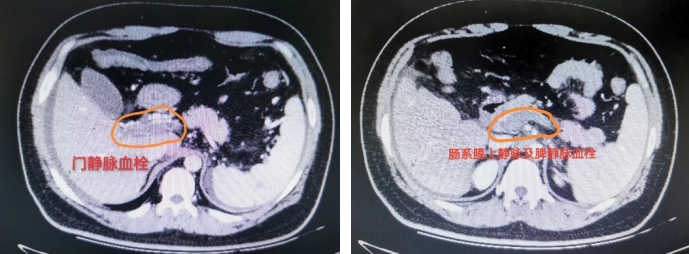

肠系膜静脉血栓形成(MVT):占比10%-15%,其核心病因是高凝状态,包括遗传性易栓症(高同型半胱氨酸血症)、获得性因素(如恶性肿瘤、腹腔炎症、肝硬化、门脉高压)以及大手术后等。

AMVT治疗后应积极避免慢性期改变:门脉海绵样变性→门脉系统静脉高压。

25岁,肥胖男性,体重125kg,主诉:腹痛10余天,加重2天、便血1天。

术中及术后标本,术后查因:诊断为高同型半胱氨酸血症 (易栓症),积极术后抗凝、随访中。

57岁,女性,主诉:腹痛5天,加重2天,急诊诊断为急性肠系膜静脉血栓形成、急性腹膜炎, WBC30000/ml以上,他院介入科行经皮门静脉肝静脉穿刺吸栓术后,仍然感染性休克。